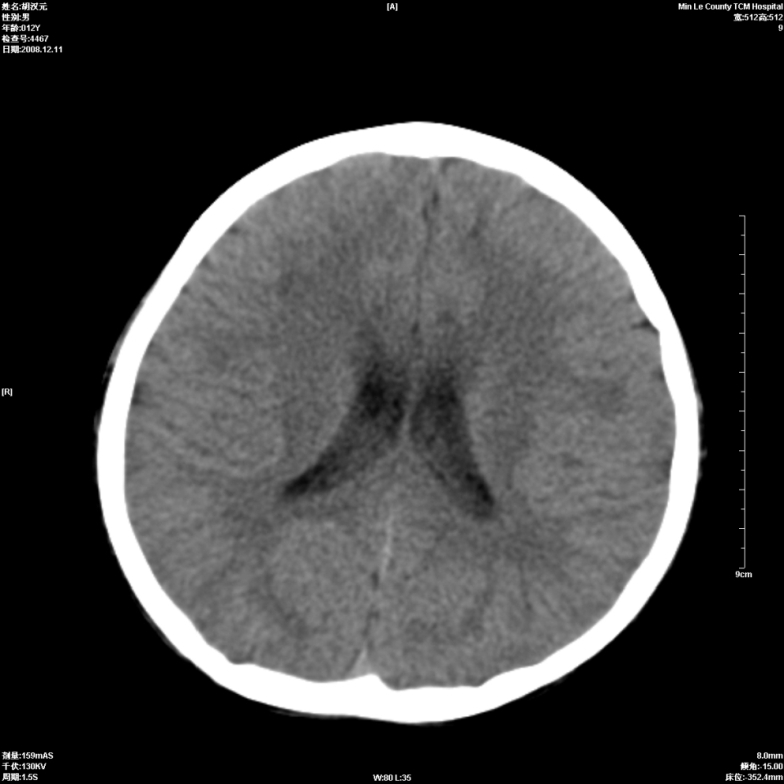

标题: PED1681:头疼发热约一周 [打印本页]

标题: PED1681:头疼发热约一周

两侧顶部近灰质处白质密度降低,是否炎性改变

颅脑ct轴位平扫颅内未见明确异常;建议必要时复查或行进一步检查。

两侧顶部近灰质处白质密度降低,建议mri